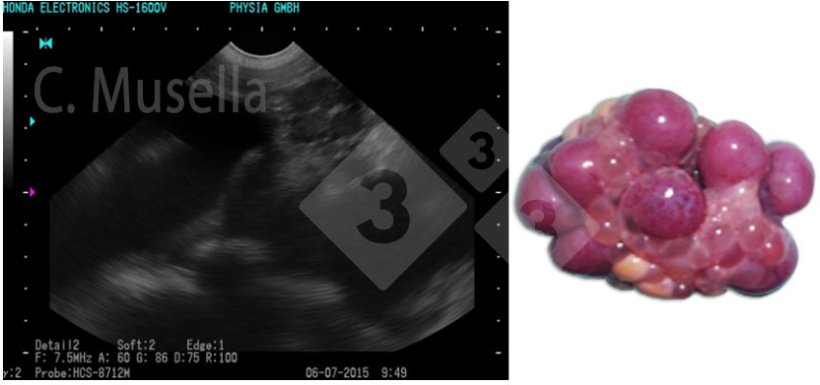

O diagnóstico de cistos ovarianos únicos ou múltiplos é relativamente simples, embora a identificação completa do tipo de cisto por ultrassom nem sempre seja certa.